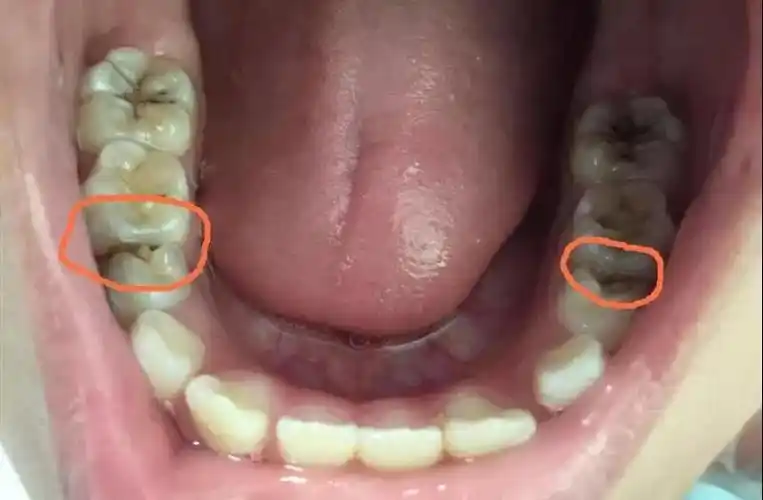

严重龋齿的图片_有来医生